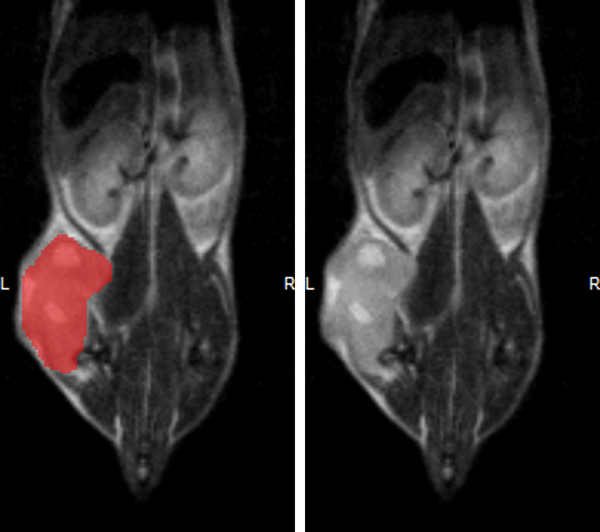

Hindlimb tumor growth: Monitoring the growth of xenograft tumor grown in the mouse hindlimb is identified with T2-weighted images. Segmentation of tumor region of interests (in red) on each tumor-containing slice allows accurate volume quantification. Image Credit: Scintica Instrumentation Inc

Monitoring the growth of xenograft tumor grown in the mouse hindlimb is identified with T2-weighted images. Segmentation of tumor region of interests (in red) on each tumor-containing slice allows accurate volume quantification. Image Credit: Scintica Instrumentation Inc